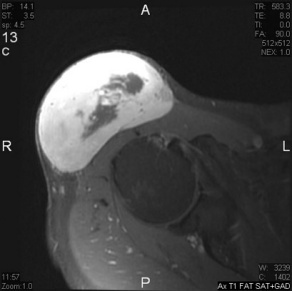

Dermatofibrosarcoma Protuberans